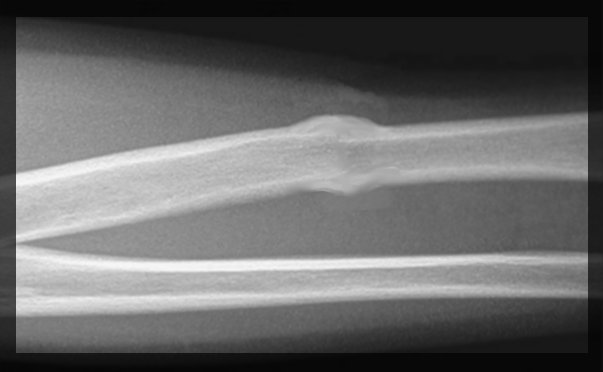

La etapa de remodelación comienza unas 6 semanas después de la lesión. En esta fase, el hueso normal sustituye al callo duro. Si vieras una radiografía del hueso en proceso de curación, tendría un aspecto irregular. Pero a lo largo de los siguientes meses, el hueso se remodela para que vuelva a tener el mismo aspecto que antes de la lesión.